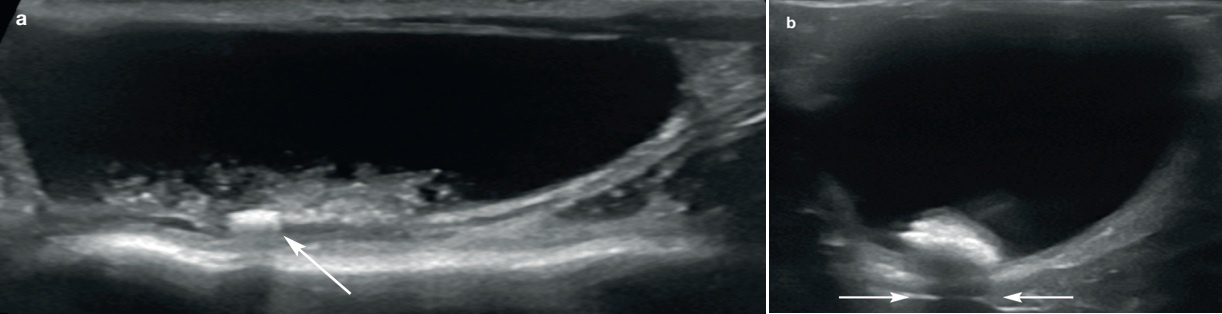

3. 방광의 스캔

초음파로 방광 크기, 벽의 두께, 장막과 점막의 경계를 잘 관찰할 수 있습니다. 방광은 후복강 내 존재하며 고양이에서 앙와위나 측와위 자세에서 쉽게 영상화됩니다. 다른 장기와 같이 2개의 직각 방향으로 스캔(시상면, 등쪽면 혹은 가로면)하며, 스캔 시 소변이 적절히 있어야 점막과 벽의 두께를 측정할 수 있습니다(그림 6).

방광의 벽은 4개의 층인, 점막층(저에코), 저막하층(고에코), 근육층(저에코)와 장막층(고에코)으로 구성되어 있습니다.

정상적인 방광의 벽 두께는 팽대되는 정도에 따라서 1.3~1.7 mm로 측정됩니다. 요관이 방광의 삼각부위로 들어가는데 요관의 유두부위가 때로는 벽 등쪽에 작은 모양으로 보입니다(그림7). 그리고 오줌이 이 유두부위를 통해서 방광으로 배출될 때 칼라 도플러로 jet 모양이 보일 수 있습니다(그림 8).